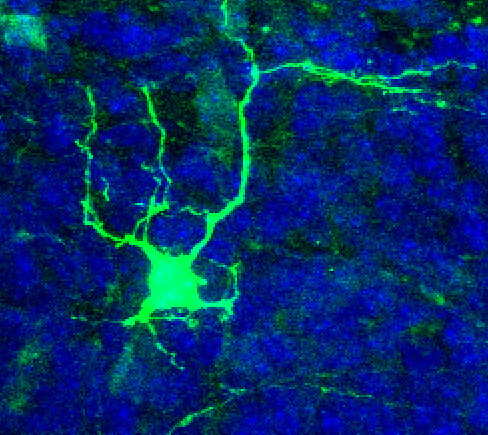

Przez 60 dni śledzono ruch i aktywność komórek. Już po czterech tygodniach neurony z obu stron pokonały po ok. 8 mm i spotkały się w środku rurki. Po dwóch miesiącach jej wnętrze było wypełnione komórkami z długimi wypustkami tworzącymi rozgałęzioną sieć, przypominającą młodą tkankę nerwową. Przeżywalność komórek przekraczała 95 procent.